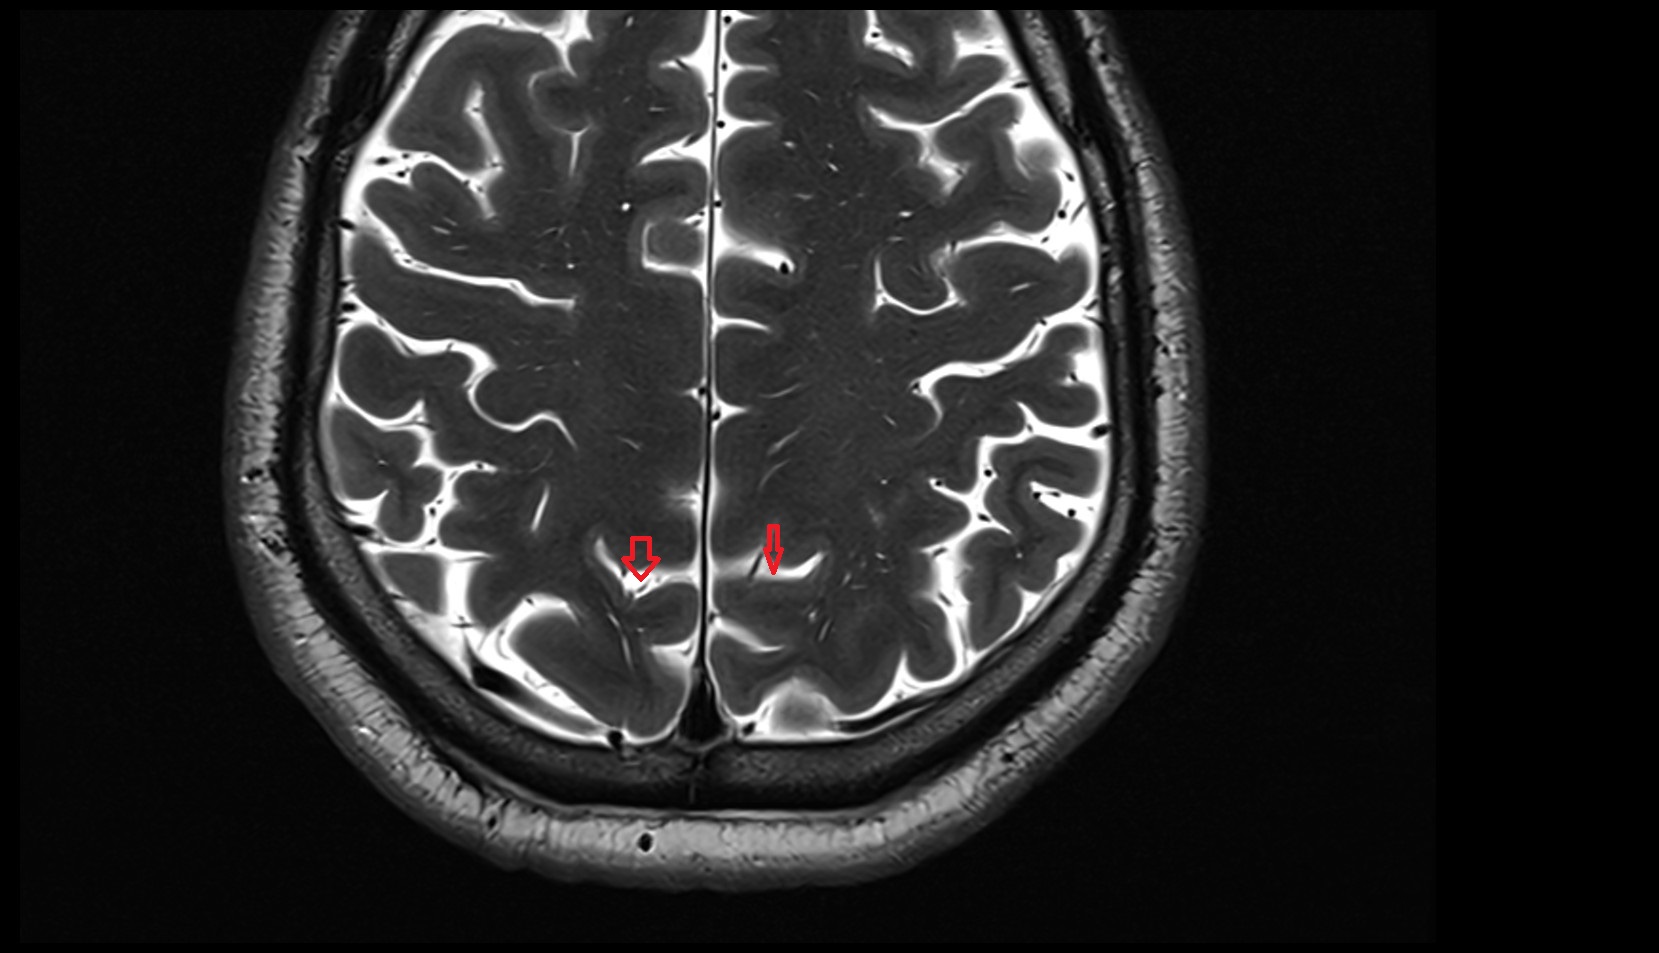

- Longitudinal cerebral fissure